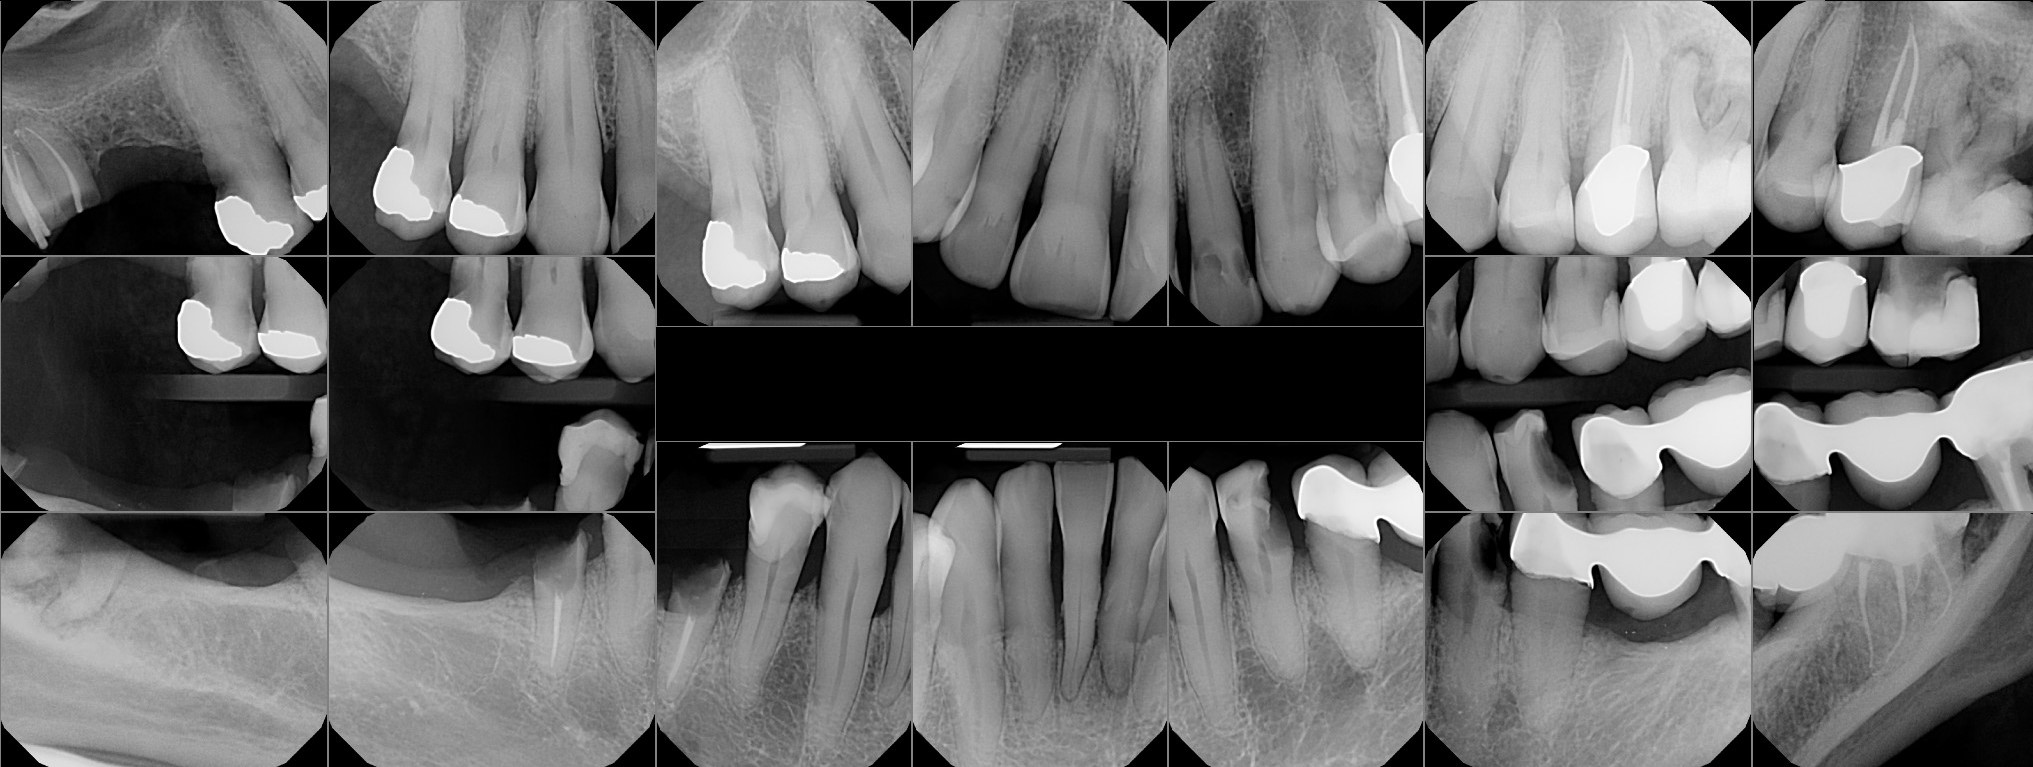

Dental Auction No. 10074: All on 6- upper and lower arches

Auction images